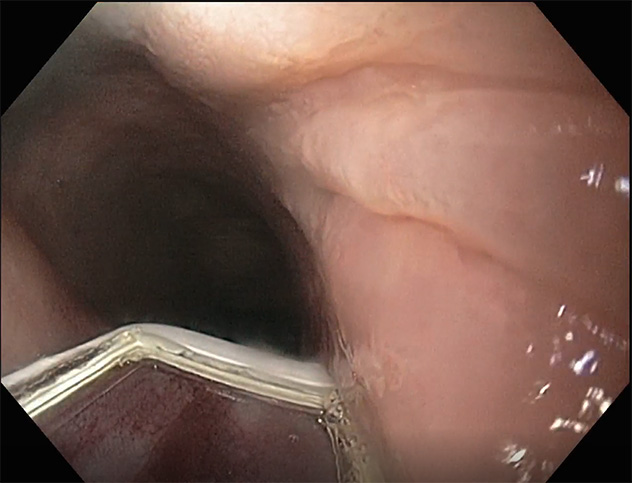

This image shows an endoscopic view of the augmented lower esophageal sphincter using a magnet closure device.

Gastroesophageal reflux disease (GERD) is a common disorder characterized by abnormal reflux of gastric contents into the esophagus, causing troublesome symptoms and mucosal damage. Our lab is developing a new anti-reflux endoscopic technique to augment the lower esophageal sphincter in a minimally invasive approach that has the unique, appealing feature of reversibility.